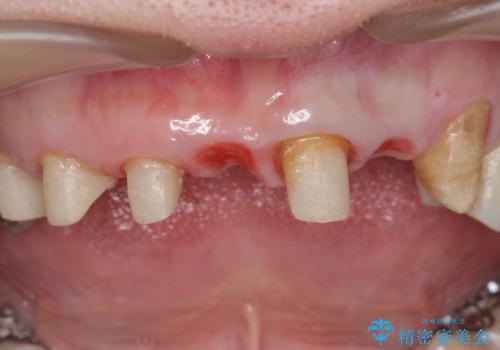

ブリッジの支台歯は、根の再治療を含めて行なっています。

- 若い時に作った前歯のブリッジがの根元が黒くなってきているとのことで来院。

支える歯が1本虫歯がひどく、割れていました。

根の治療からやり直して新しいブリッジにしています。